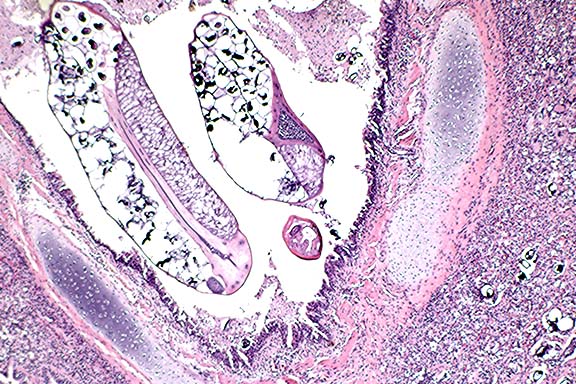

Contributor's Diagnosis and Comments: Mediastinal lymph node: Chronic multifocal granulomatous lymphadenitis with intralesional green algal forms.

Morphologic description: There are multifocal infiltration, expansion, and replacement of normal lymph node structure by aggregates of epithelioid macrophages, multinucleate giant cells, and plasma cells. The two former cells often contain numerous cytoplasmic algal forms characterized by: single ovoid structures (8-12 microns) with granular basophilic central material and a dense eosinophilic cell wall, similar structures without central basophilic material and with cleavage (endosporulation into 4-8 ellipsoid forms) within the cell wall. The organisms contain numerous coarse anisotropic and periodic acid-Schiff positive granules (starch granules). Impression smears of fixed lymph node reveal green oval organisms on unstained smears, and similar organisms on H&E- and Giemsa- stained smears are green in color. There were numerous coarse anisotropic granules in the organisms on smears.

Conference Note: GMS and PAS stains performed at the AFIP revealed numerous cytoplasmic granules in the organisms. Also, the granules remained PAS-positive after diastase treatment. This finding differs from a previous report by Chandler et al1, who stated that these granules were PAS-negative following diastase digestion. They also noted that similar granules are present in Protothecacells, but in much lower numbers, and the granules are smaller and less distinct. Ultrastructurally, Chlorella cells contain chloroplasts, consisting of irregularly shaped cytoplasmic granules surrounded by membranes stacked in alternating bands of two to five lamellae. True chloroplasts have not been found in Prototheca. In the absence of gross pathologic findings and special staining techniques, it remains difficult or impossible to differentiate green algae and Prototheca cells in tissue stained by H&E.

Prototheca spp., thought by some to be achloric mutants of the genus Chlorella, include two species known to be pathogenic in animals and man, P. zopfiiand P. wickerhamii. These organisms are found in soil, water, tree sap, potato skin, sewage, and feces of pigs and humans. Prototheca generally causes progressive granulomatous lesions in numerous animal species. Lesions include cutaneous infections in cats and humans, mastitis in cows, and disseminated infections in dogs. The intestine and the eye are the most commonly involved sites in canine protothecosis.